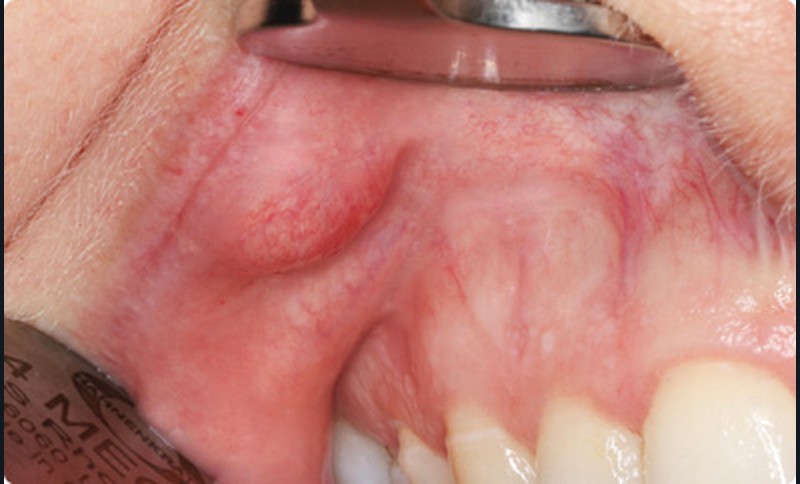

- Cette patiente avait une très bonne hygiène bucco- dentaire et présentait deux arcades dentaires indemnes de caries et de soins. Dans la lèvre supérieure droite, on palpait un nodule sous-muqueux, indolore, ferme, bien limité, mobile, arrondi, de 4 mm de diamètre. Lorsque la muqueuse était mise en tension, il prenait une couleur jaunâtre.